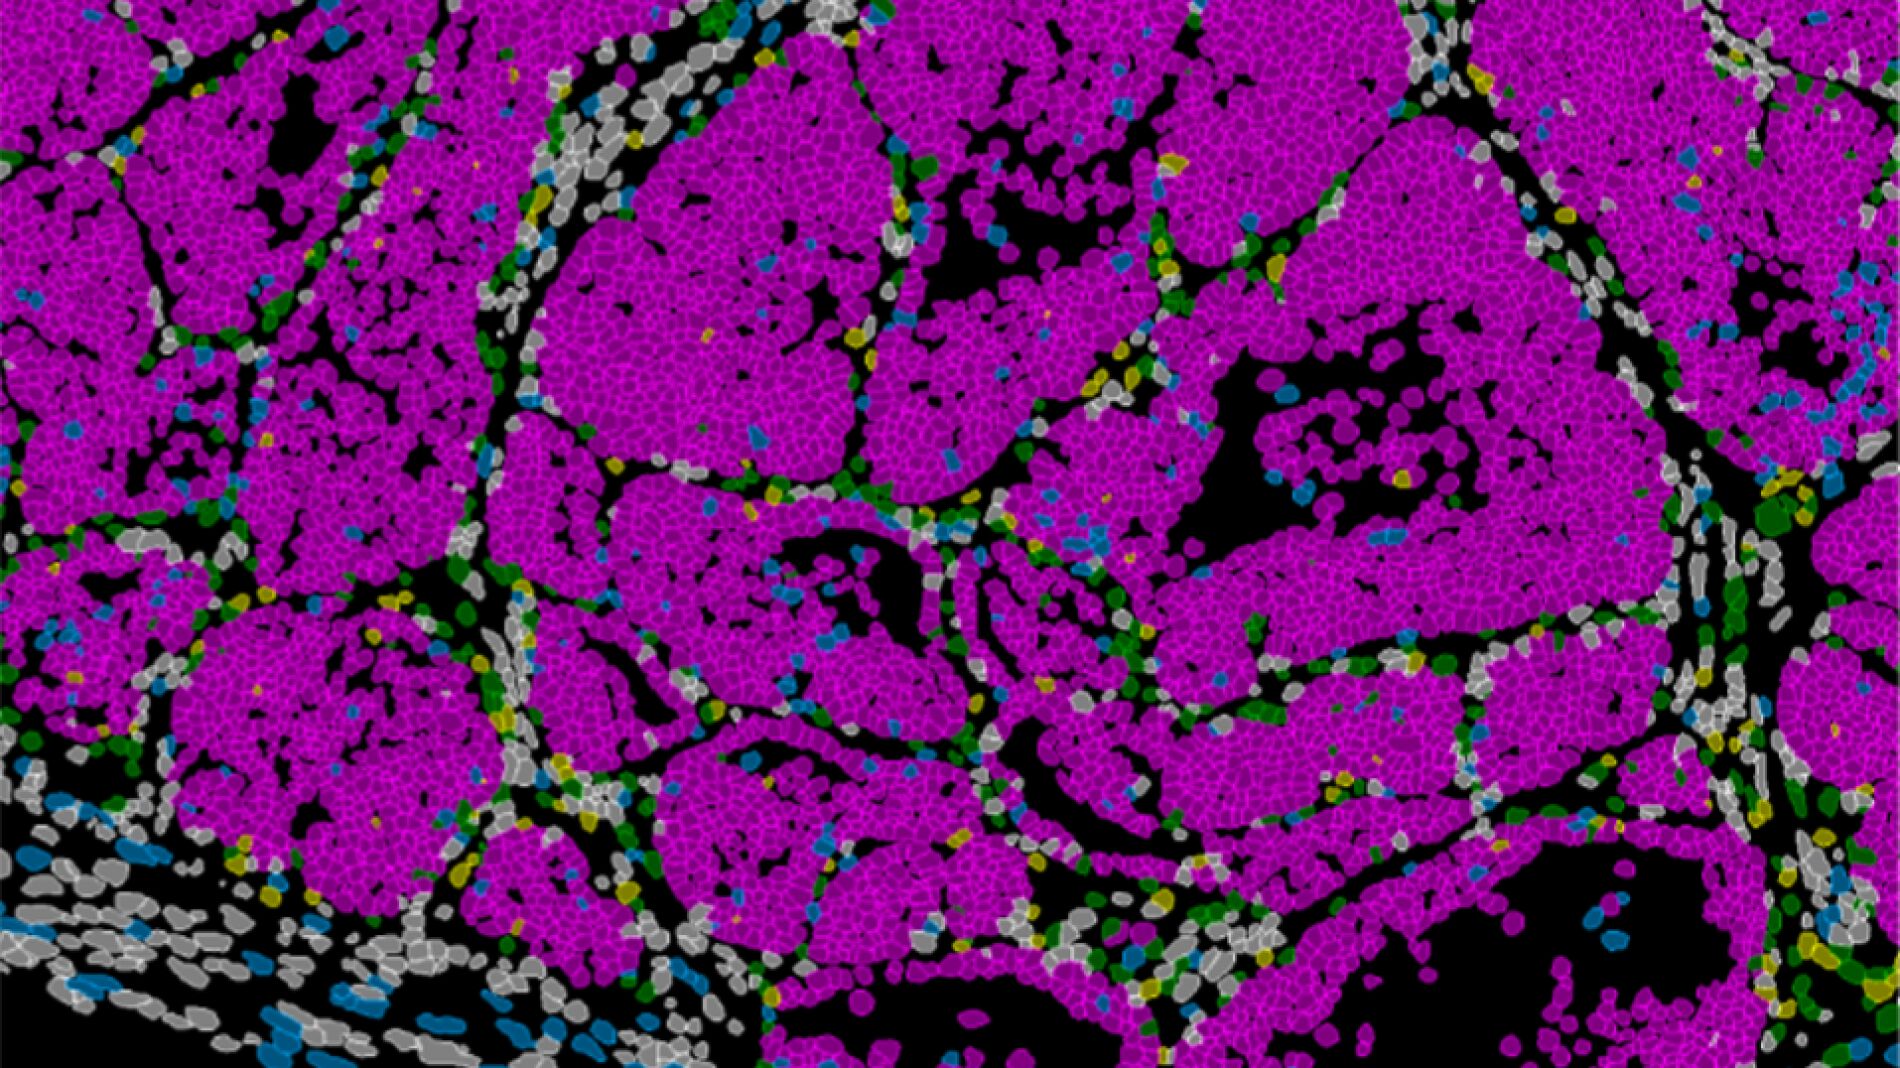

Este estudio demuestra que la capacidad metastática no surge por azar...